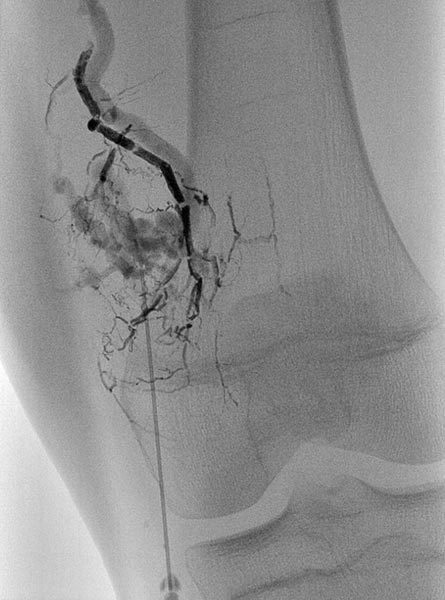

Die digitale Subtraktionsangiographie (DSA) in der früharteriellen Phase zeigt eine, aufgrund der chronischen Mehrdurchblutung erweiterte, zuführende Arterie (sogenannte Feederarterie), in diesem Fall eine Arteria genu superior medialis.

Die digitale Subtraktionsangiographie (DSA) in der arteriellen Phase 2 s später zeigt einige kleinere arteriovenöse Fisteln.

Die digitale Subtraktionsangiographie (DSA) in der arteriellen Phase zeigt im Gegensatz zu einer arteriovenösen Malformation nochmals 4 s später keinen direkten frühvenösen Abstrom des Kontrastmittels, sondern eher ein Pooling-Phänomen.

Superselektive Sondierung der Arterie mit einem Mikrokatheter zeigt wiederum die multiplen, feinen arteriovenösen Fisteln, jedoch nicht den für eine AVM typischen sofortigen venösen Abstrom. Diese starken arteriovenösen Fisteln in die VM sind ungewöhnlich ausgeprägt.